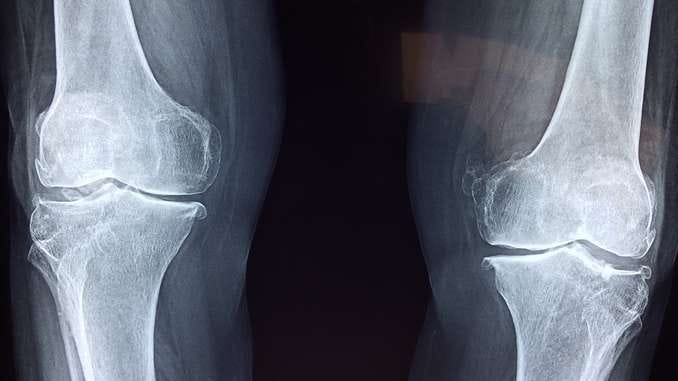

Bone Therapeutics diffère des précédentes biotechs (Ablynx, Argen-x, Asit et Biocartis) par sa spécialisation. La société de Gosselies se centre en effet sur la thérapie cellulaire osseuse.

Quand on connaît la forte prévalence des maladies osseuses et orthopédiques dans la population, il est évident que la biotech cible un public important.

Bone Therapeutics recourt à une méthodologie très spécifique et peu invasive. Le prélèvement cellulaire (souches de moelle osseuse) s’opère à partir de sujets sains et fait ensuite l’objet de recherches et d’expériences ex-vivo (« en dehors du vivant »).

Deux types de produits coexistent dans le pipeline de Bone Therapeutics : l’ALLOB (fusion vertébrale, actuellement en phase IIA ; fractures avec retard de consolidation, actuellement en phase IIIA), et le PREOB, destiné (outre la maladie des os de verre) à la nécrose osseuse de la hanche. Mais ces traitements sont promis à de futures extensions d’indications et de développement. En ce sens, l’espoir est important de voir se renforcer le pipeline.

Une spécificité dans le domaine des maladies osseuse et orthopédiques, via une technologie unique et peu invasive.